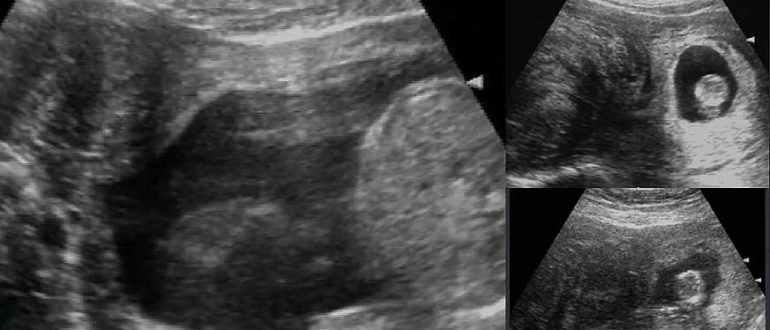

Миома или беременность

Как протекает беременность при миоме? Миома матки представляет собой одну из самых распространенных разновидностей опухолей, диагностирующихся в женской репродуктивной системе. Она диагностируется как у молодых женщин, так и…